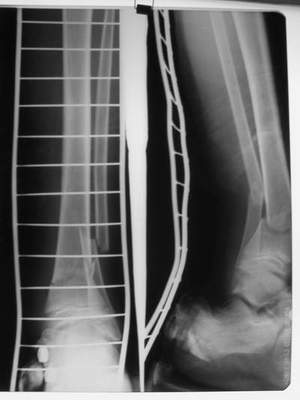

A> Перелом костей н\3 правой голени со смещением.

A> Перелом большеберцовой

A> кости можно охарактеризовать как компрессионно-оскольчатый.

A> В январе 2005: варусная деформация н\3 голени,

A> Операции: 1 Клиновидная резекция на вершине деформации м\берцовой кости.

A> 2 Тугоподвижный ложный сустав н\3 б\берцовой кости.

A>> Перелом костей н\3 правой голени со смещением.

Есть даже тень периостальной костной мозоли и сросшийся перелом

малоберцовой кости.

Это сросшийся перелом малоберцовой кости. И ложный сустав

н\3 б\берцовой кости.

Так как речь зашла непосредственно о травме, см этапные

снимки. Как все было

Первичные

Вытяжение

Фиксация

в гипсе

Промежуточный